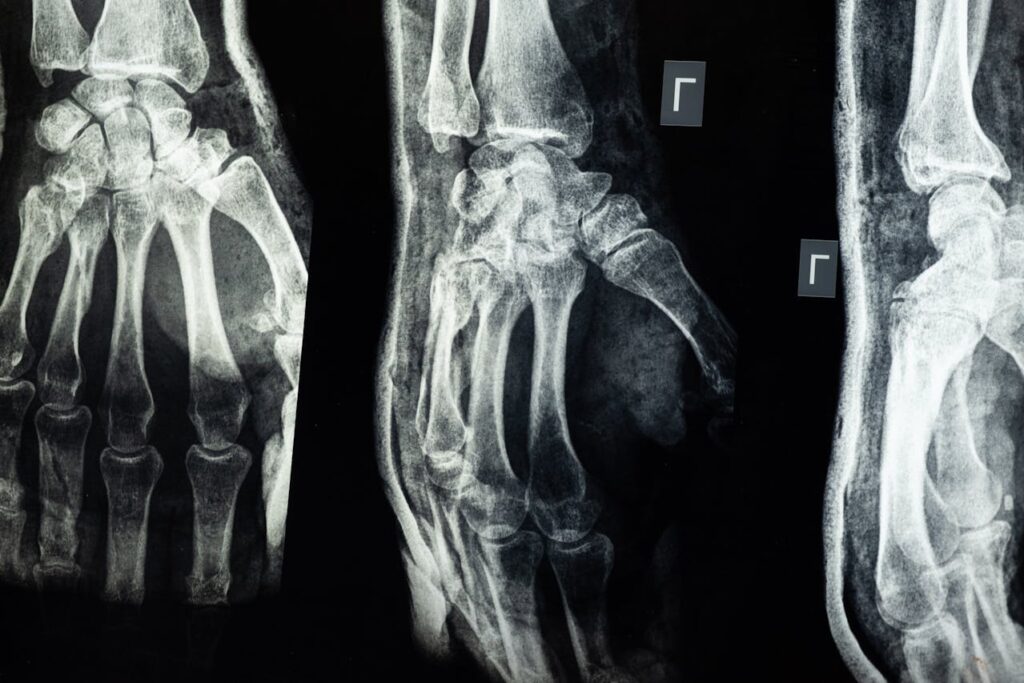

Pols, enkel en vinger breuken beperken je direct

Een gebroken pols, enkel of vinger lijkt minder ernstig, maar dat klopt niet. Deze botten zorgen juist dat je dingen kunt vasthouden, lopen of schrijven. Breek je hier iets, dan voel je het bij elke kleine beweging. Iets oppakken, typen of zelfs tandenpoetsen kan plotseling flink veel pijn doen. Vooral bij een verschoven breuk kost het herstellen nog meer tijd en moeite.